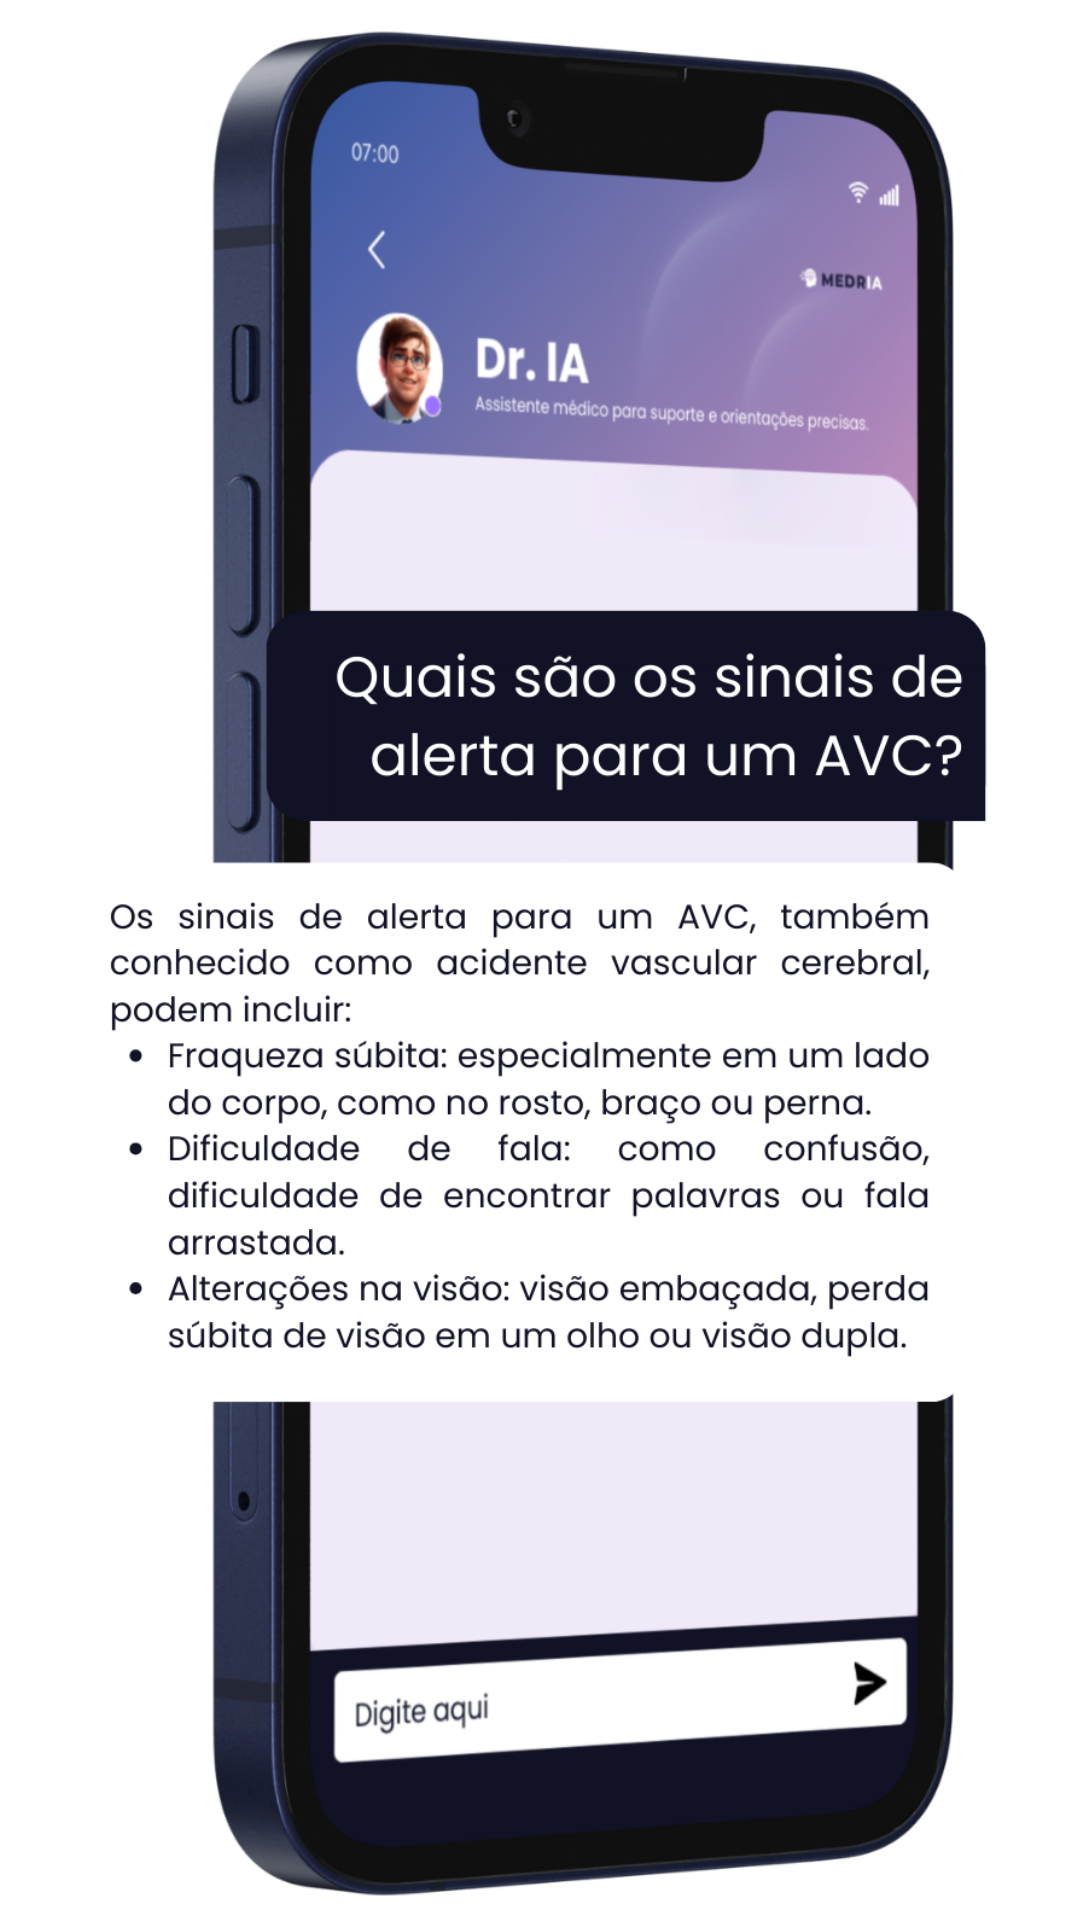

Assistente inteligente

Desenvolvido com base em uma biblioteca médica extensa e atualizada, feita para acompanhar os desafios reais da prática clínica.

Respostas clínicas em segundos, conteúdo técnico e confiável sempre disponível para te apoiar — um parceiro para decisões seguras.

Chat com assistente de saúde (IA), histórico e organização de informações pessoais além de dicas de autocuidado baseadas em evidências.